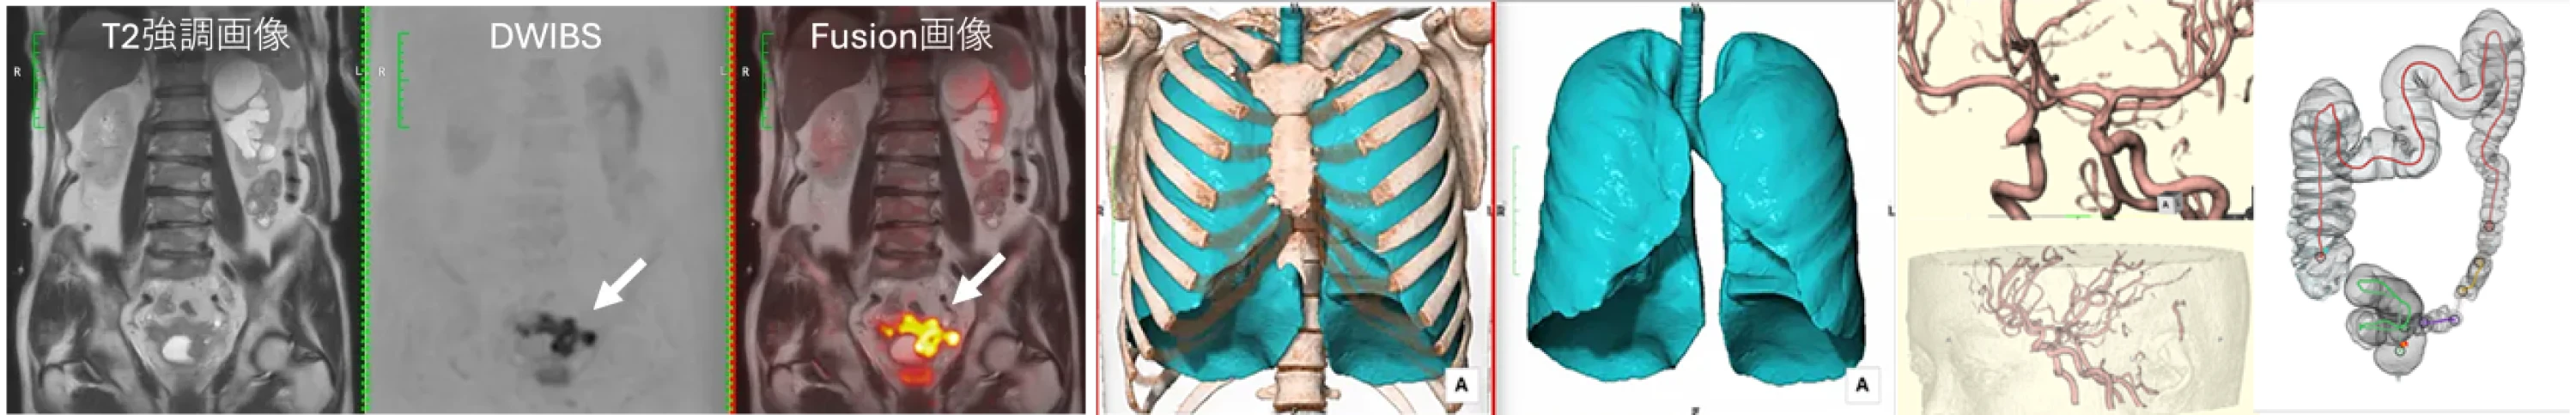

高原クリニック イノベーティブスキャンのMRIは、すい臓がんの早期発見において高精度な診断を実現しています。